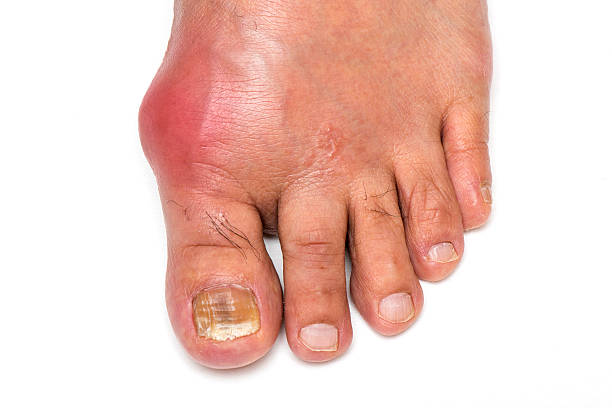

급성 통풍 발작은 갑작스럽게 발생하며, 대개 하루 이내에 최대 발생점에 도달합니다. 발작이 발생하면 통증이 극심하게 시작되고, 발적 부위는 붉고 따끔거리며 따끔거리고, 적출물로 인해 부어오릴 수 있습니다.

급성 통풍 발작은 관절 내부에서 염증이 발생합니다. 이는 염증을 일으키는 화학 물질이 적출물로 발적 주위에 축적되기 때문입니다. 염증은 일반적으로 통증, 붓기, 붉어짐 등을 초래할 수 있습니다.

발적

발적 부위는 붉고 따끔거리며, 적출물로 인해 부어오를 수 있습니다. 이러한 발적은 대개 발작이 발생하는 부위에 나타나며, 발적이 심한 경우 걷는 것이 어려울 수 있습니다.